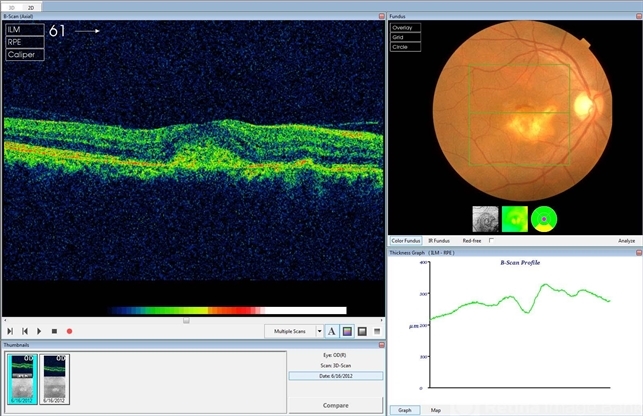

- choroidal osteoma, choroidal neovascularization (CNV), optical coherence tomography (OCT)

- Hamid Ahmadieh, Ophthalmic Research Center, Labbafinejad Medical Center

- Topcon

- Color fundus photograph and OCT imaging of a 47-year-old man with a juxtafoveal CNV superimposed on a choroidal osteoma.